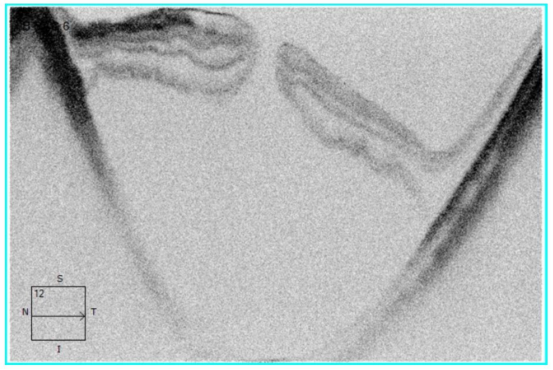

术前OCT